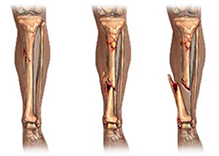

Se in una frattura i due monconi ossei non si spostano e mantengono, quindi, l’asse anatomico originale, si parla di frattura composta. Solitamente le fratture composte hanno una adeguata stabilità intrinseca che ne garantisce una buona guarigione; esse verranno trattate, pertanto, conservativamente, ovvero con un semplice gesso o tutore esterno.

Nel caso in cui la frattura determina lo spostamento dei due (o più) frammenti ossei, si parla di frattura scomposta. In questo caso si renderà necessaria una manovra di riduzione che ristabilire i corretti rapporti anatomici.

La manovra riduttiva, applicando una trazione manuale sul segmento fratturato, permetterà il corretto allineamento dell’osso. Se tale manovra non risulta efficace o qualora la frattura risulta instabile nonostante l’immobilizzazione con gessi o tutori, si renderà necessario un intervento chirurgico per riallineare la frattura e renderla stabile.